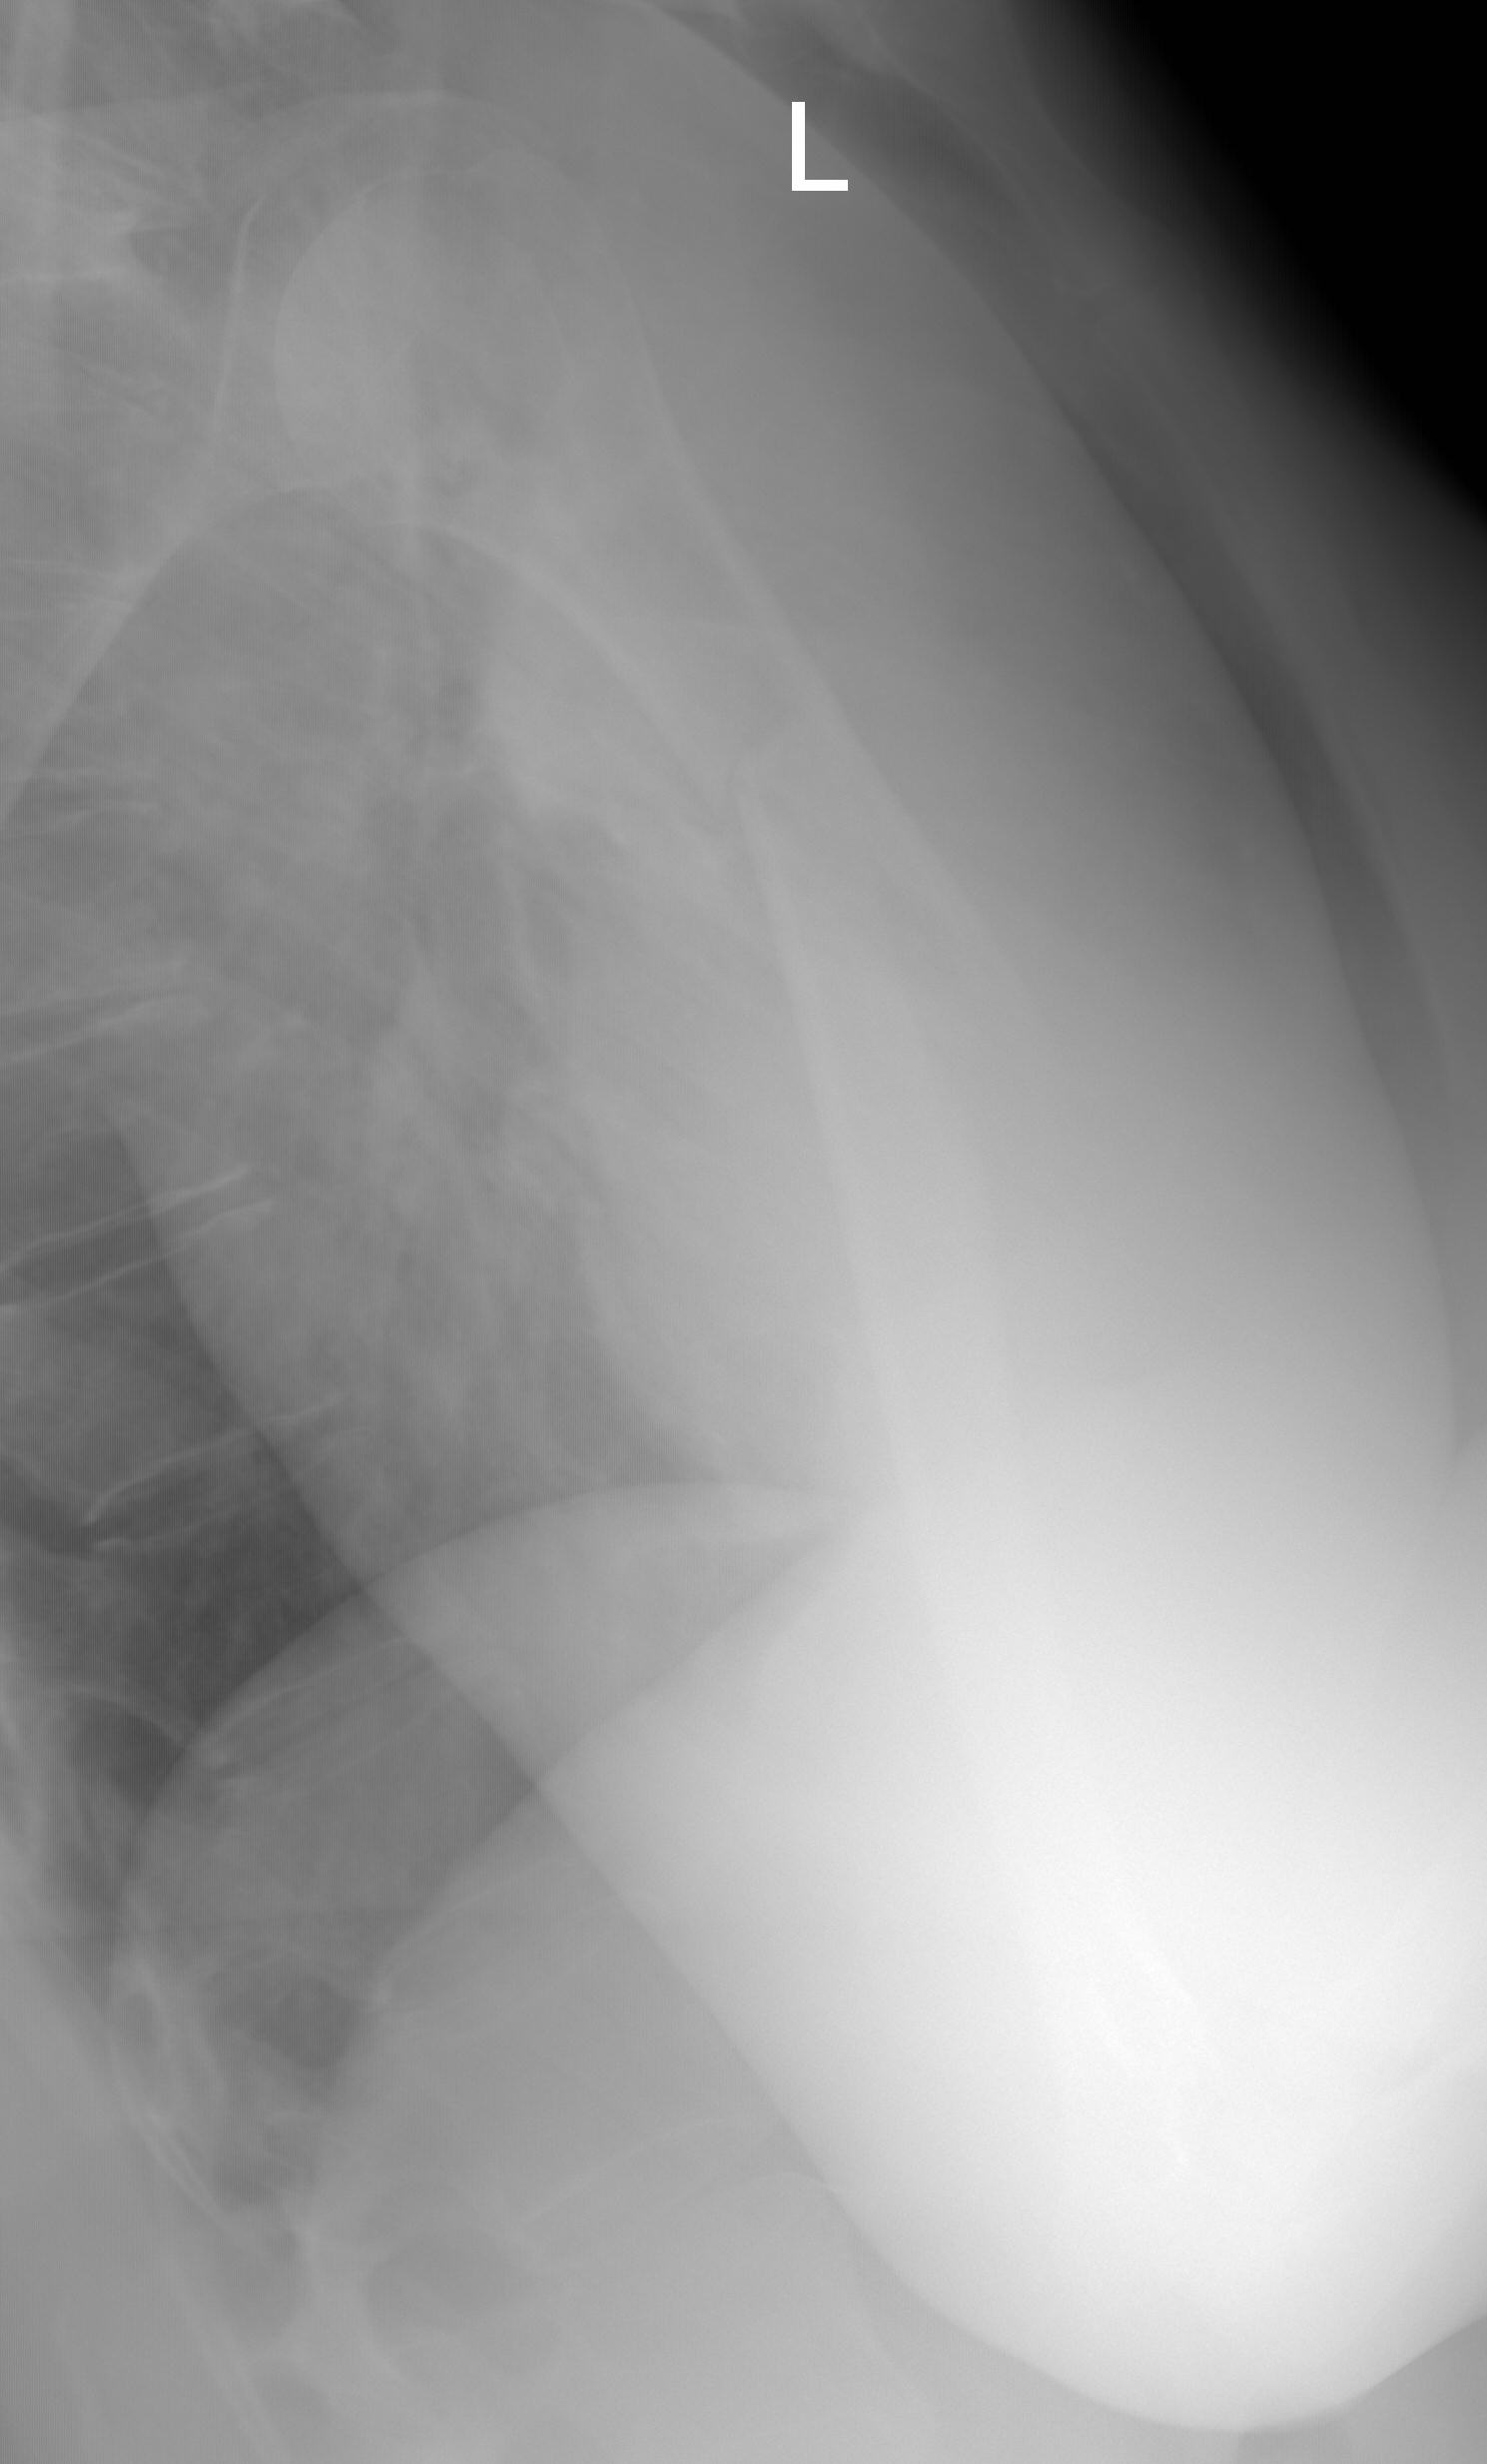

[Ortho] Нестабильность остеосинтеза, несращение перелома плечевой кости.

Еще Рентгенограммы